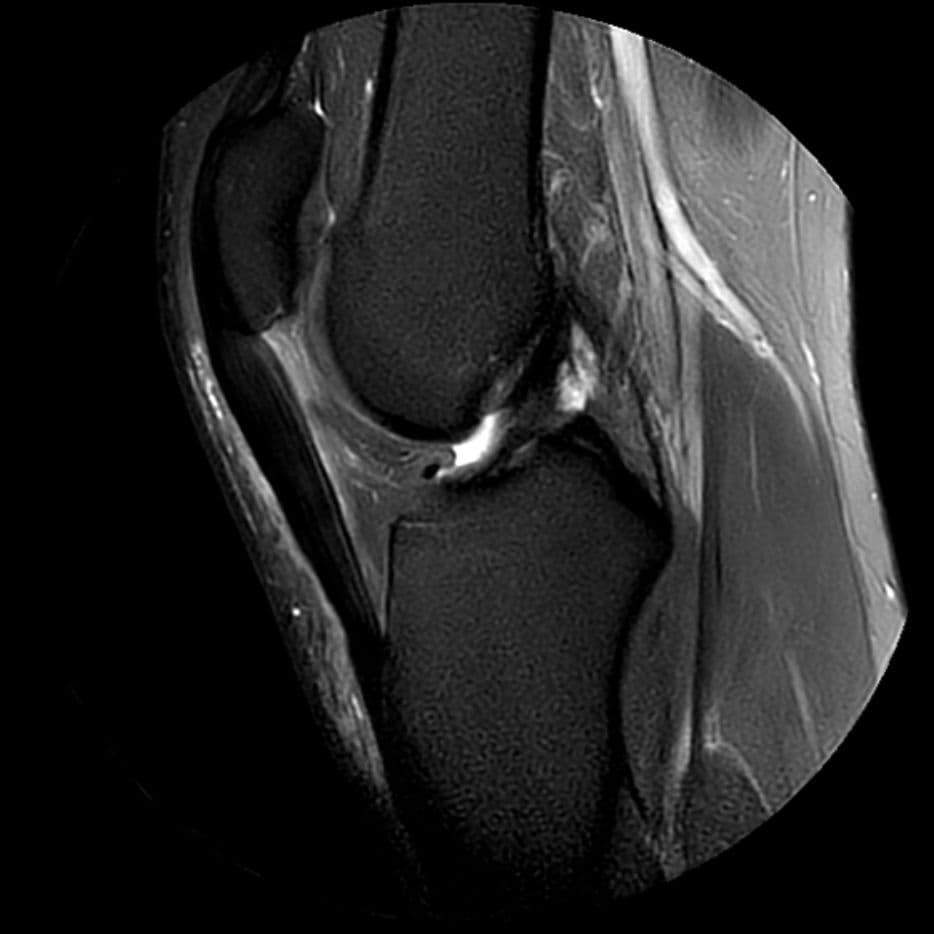

Patient de 33 ans, douleurs antérieures chroniques avec gonflement. Aspect IRM d'une enthésopathie proximale du tendon patellaire.

MRI